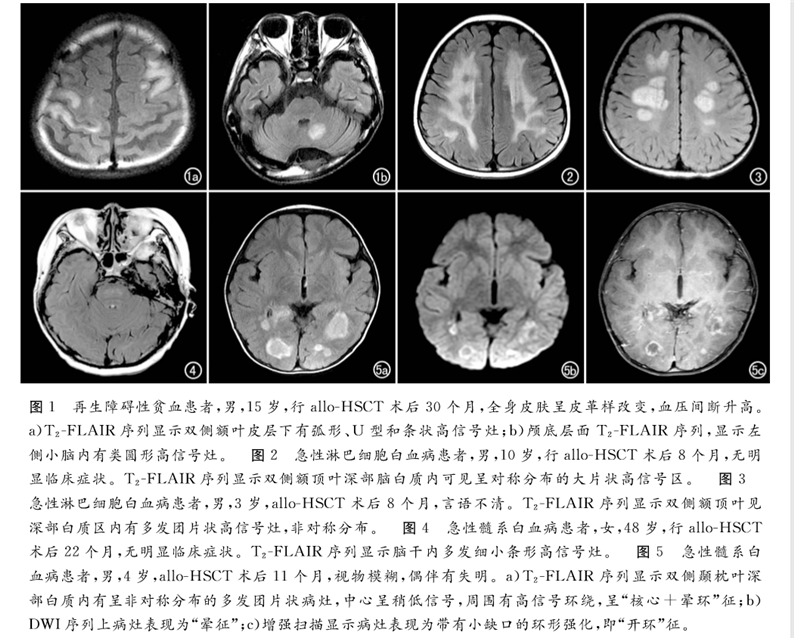

论文回顾性分析了2013年6月—2017年12月北京陆道培医院确诊为allo-HSCT后并发中枢神经系统慢性移植物抗宿主病的12例血液病患者的临床和影像学资料。得出结论,MRI是发现血液病异基因造血干细胞移植(allo-HSCT)后并发中枢神经系统慢性移植物抗宿主病的有效手段,可以提高对本病的诊断及鉴别水平,为临床制订佳治疗方案提供帮助。